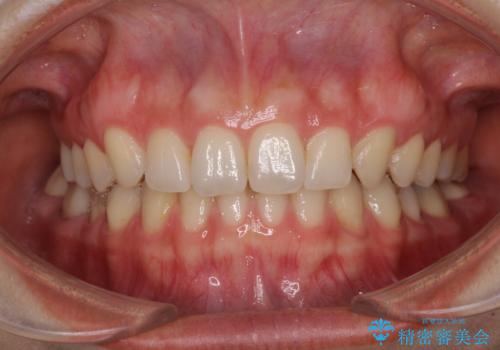

- 前歯のデコボコを治したいとのことで来院された患者様です。

上下顎ともに歯列全体の側方拡大とIPR(歯と歯の間を削る)によってデコボコが解消するように設計し、インビザラインにより治療を行うこととしました。